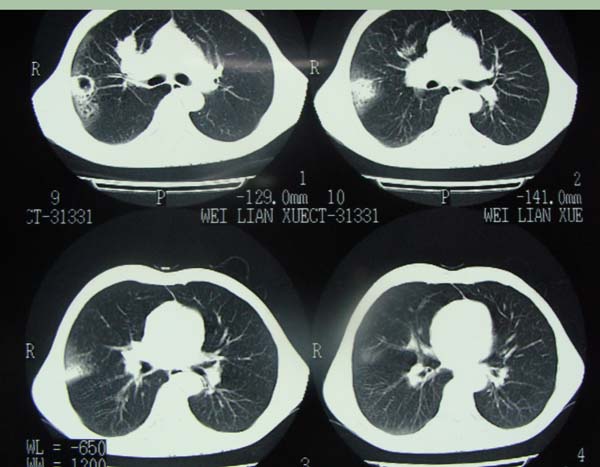

以下是引用pujunzhi在2009-6-21 21:48:00的发言:[br]右肺上叶后段见一空洞性病灶,灶周有渗出即晕征,右肺门肿大---可考虑感染性空洞和癌性空洞,先抗炎抗痨后复查并完善相关检查。有癌性空洞伴肺门淋巴结转移的可能。